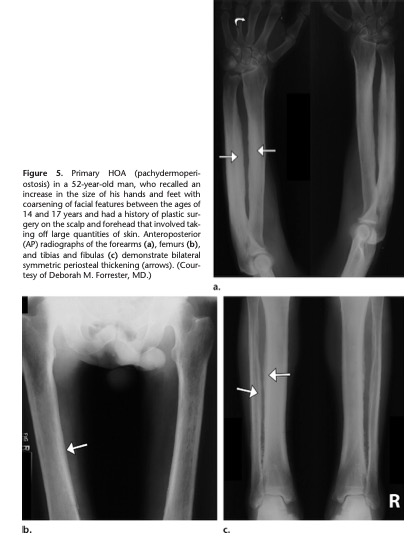

画像の例 (RadioGraphics 2017; 37:157–175)

・原発性HOAの症例. 両側性の骨膜症・25歳の肺膿瘍による続発性HOA 両側性の脛骨, 腓骨の骨膜症を認めるHOAの鑑別で重要な疾患